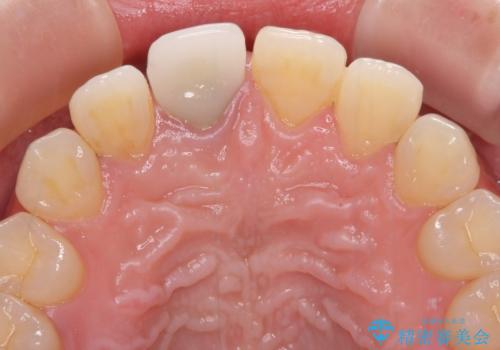

不自然なセラミッククラウンを自然なセラミックに

- 近医にて被せた前歯のクラウンの色の違いを気にして来院された患者様です。

オーダーメイドのオールセラミッククラウンにて補綴することとしました。

元々すきっ歯であったため、隙間を全て埋めると左右で大きさがアンバランスとなることが懸念されました。

違和感のない程度に隙間を小さくして、自然な見た目に仕上げました。